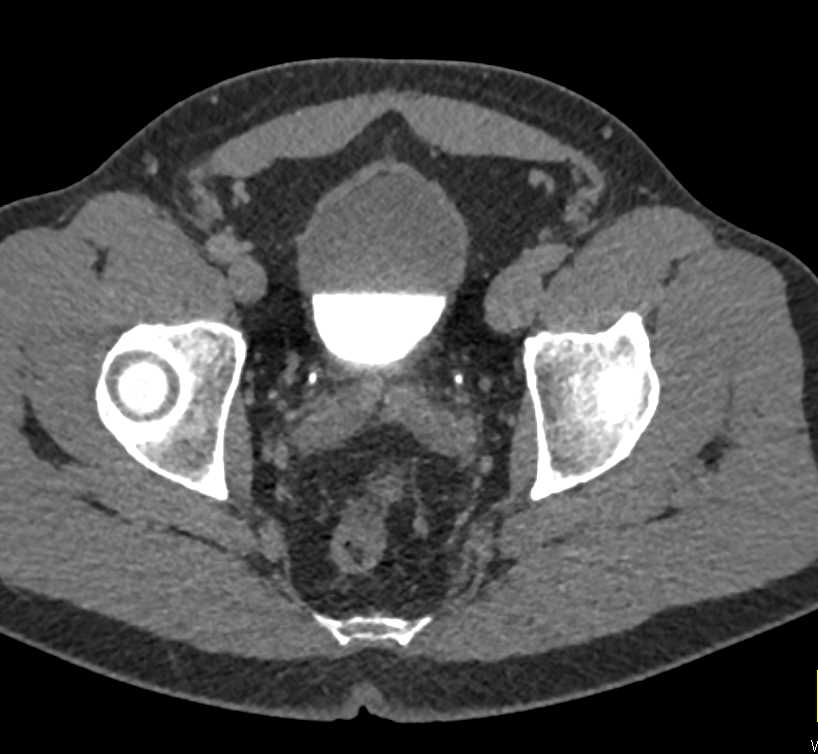

Bladder Cancer Left Bladder Wall